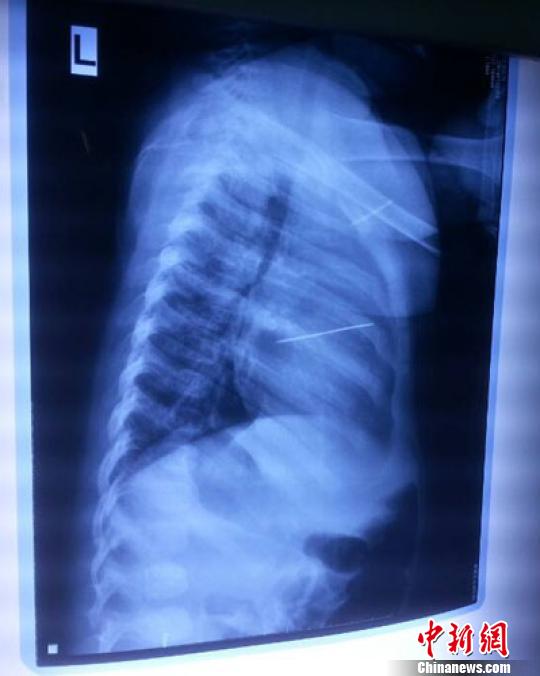

女嬰胸片提示心臟里面扎了一個(gè)縫衣針 蔡迅翔 攝

醫(yī)院胸心外科主任翟波介紹說(shuō),1月22日,小患者彤彤因?yàn)榘l(fā)燒抽搐來(lái)醫(yī)院就診,常規(guī)檢查時(shí)發(fā)現(xiàn)孩子心臟里面扎了一個(gè)縫衣針。

“第二天上午,我們做了個(gè)緊急彩超檢查,發(fā)現(xiàn)針是從患者右心室表面刺入,穿破室間隔,到達(dá)左心房,中間還有一部分損害到二尖瓣。于23號(hào)下午,我們就做了一個(gè)緊急手術(shù),手術(shù)中發(fā)現(xiàn),這枚針已經(jīng)刺入心臟,沒(méi)入了右心室的下面,表面已經(jīng)看不到針了,僅能看到一個(gè)小針眼,還在往外滲血,一點(diǎn)一點(diǎn)的滲,心包腔里面大概有100多毫升的出血,心包上一個(gè)洞,針在右心室表面刺入以后,穿過(guò)室間隔,在二尖瓣的上方,進(jìn)入了左心房,在針的四周,有很多纖維沉積物,包繞著這枚針。”翟波說(shuō),他們把針取出來(lái)以后,測(cè)量了一下,長(zhǎng)度大概是五厘米,同時(shí)發(fā)現(xiàn)這個(gè)針給患者左心房的后壁造成了一定的損傷,左心房的后壁已經(jīng)損傷了三分之二,還剩下有左心房的外膜,很薄的一層,如果這一層再破的話,這個(gè)孩子將會(huì)引起大出血,很快就會(huì)死亡。